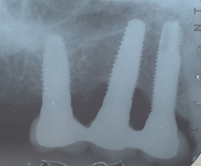

Moderada: Profundidad de sondaje >6 mm, con sangrado y/o supuración en >2 sitios del implante, y pérdida ósea entre 25% - 50% del largo del implante (Fig. 3).